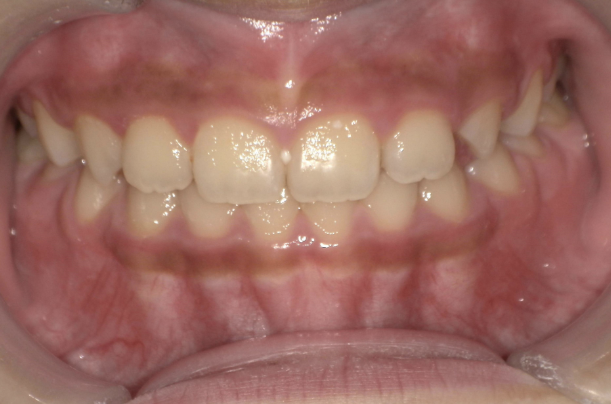

10歳を過ぎてからの矯正治療の場合、大人の歯を抜いて治療することが多くなります。 一方、下の前歯が生えてくる5〜7歳頃から治療を始めると、大人の歯を抜かずに治療することが可能です。 抜かずに治療するには早期に治療を開始することが大切です。

歯並びが悪いのは、あごの骨が成長不足で小さいことで起こります。 当院で行なっているこどもの歯ならび治療はあごの骨に働きかけることができます。 骨に働きかけることで成長不足のお子さんの骨が成長して、顔つきが良い方向に変わっていく可能性があります。 実は大きくなってからの矯正治療は歯が並んでいるだけで骨やお顔つきは変わっていないのです。 5〜7歳ぐらいで治療を開始すると成長不足の骨に働きかけて、より良い顔つきになれる可能性があります。

反対咬合(受け口)の治療も

※治療結果には個人差があります。